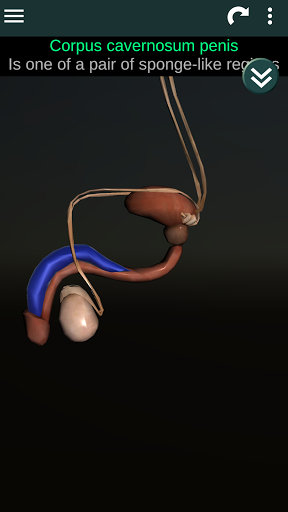

Shows a 3D anatomical model of the main organs of the human body and a description of each one.

* Reproductive system, which includes the male and female reproductive organs.

* Easy to access and navigate (zoom, 3D rotation).

* Compare male and female organs.

* Descriptions of each organ.